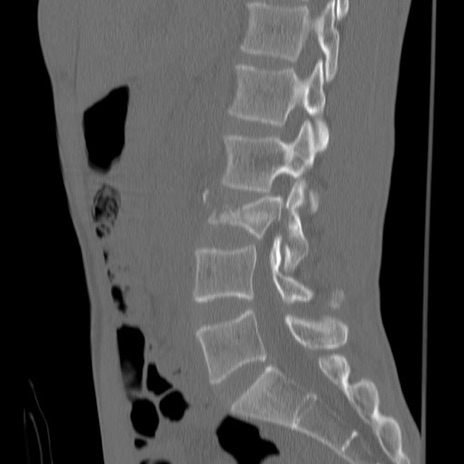

症例3 腰椎CT(矢状断像)

【症例】30歳代男性

【主訴】腰痛

【現病歴】本日旅行先で観光中に、友人と衝突し転倒し受傷。

【身体所見】麻痺なし、右下腿内側前面外側、左下腿内側に知覚鈍麻・しびれ

異常所見と診断は?

腰椎CT